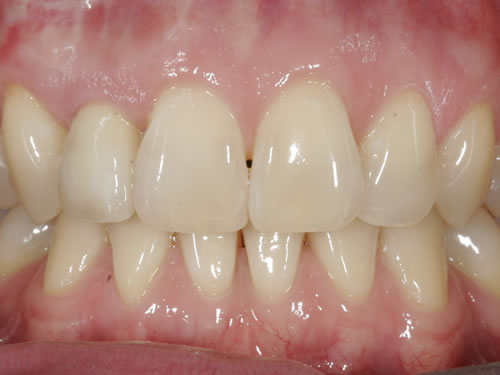

Eine besondere Herausforderung ist die Oberkieferfrontzahnregion. Der Wunsch nach einem perfekten Resultat ist geradezu selbstverständlich. Jeder möchte große, weiße Zähne und ein gesundes, reizloses Zahnfleisch besitzen (Abb. 3.30).

Abb. 3.30: Perfektes Resultat einer Versorgung.

Häufig führt ein Zahnverlust zu einem Verlust von Knochen (Hartgewebe) und der bedeckenden Schleimhaut (Weichgewebe). Besonders im sichtbaren ästhetisch sensiblen Bereich ist es aber notwendig, dass sowohl Hart- als auch Weichgewebe so wiederhergestellt wird, dass im Idealfall das Zahnimplantat mit seiner Krone dem Aussehen des ehemaligen gesunden Zahn entspricht. Als Erfolgskriterien werden aus zahntechnischer Sicht die Form, Farbe und Größe der individuellen Krone angesehen. Aus medizinischer Sicht gibt es wichtige Erfolgskriterien, die die Implantatposition, die Implantatlänge, den Implantatdurchmesser, den Zahnfleischrand im Vergleich zum Nachbarzahn und die Zahnfleischpapillen zwischen den Zähnen beinhalten. Zusätzlich braucht man ein zahntechnisches Labor, das mit der Keramikverarbeitung ein natürliches Aussehen gestalten kann. Nur, wenn alle Parameter perfekt sind, ist das Ergebnis perfekt. Das macht den Einzelzahnersatz im Oberkieferfrontzahngebiet zu einer echten Herausforderung.